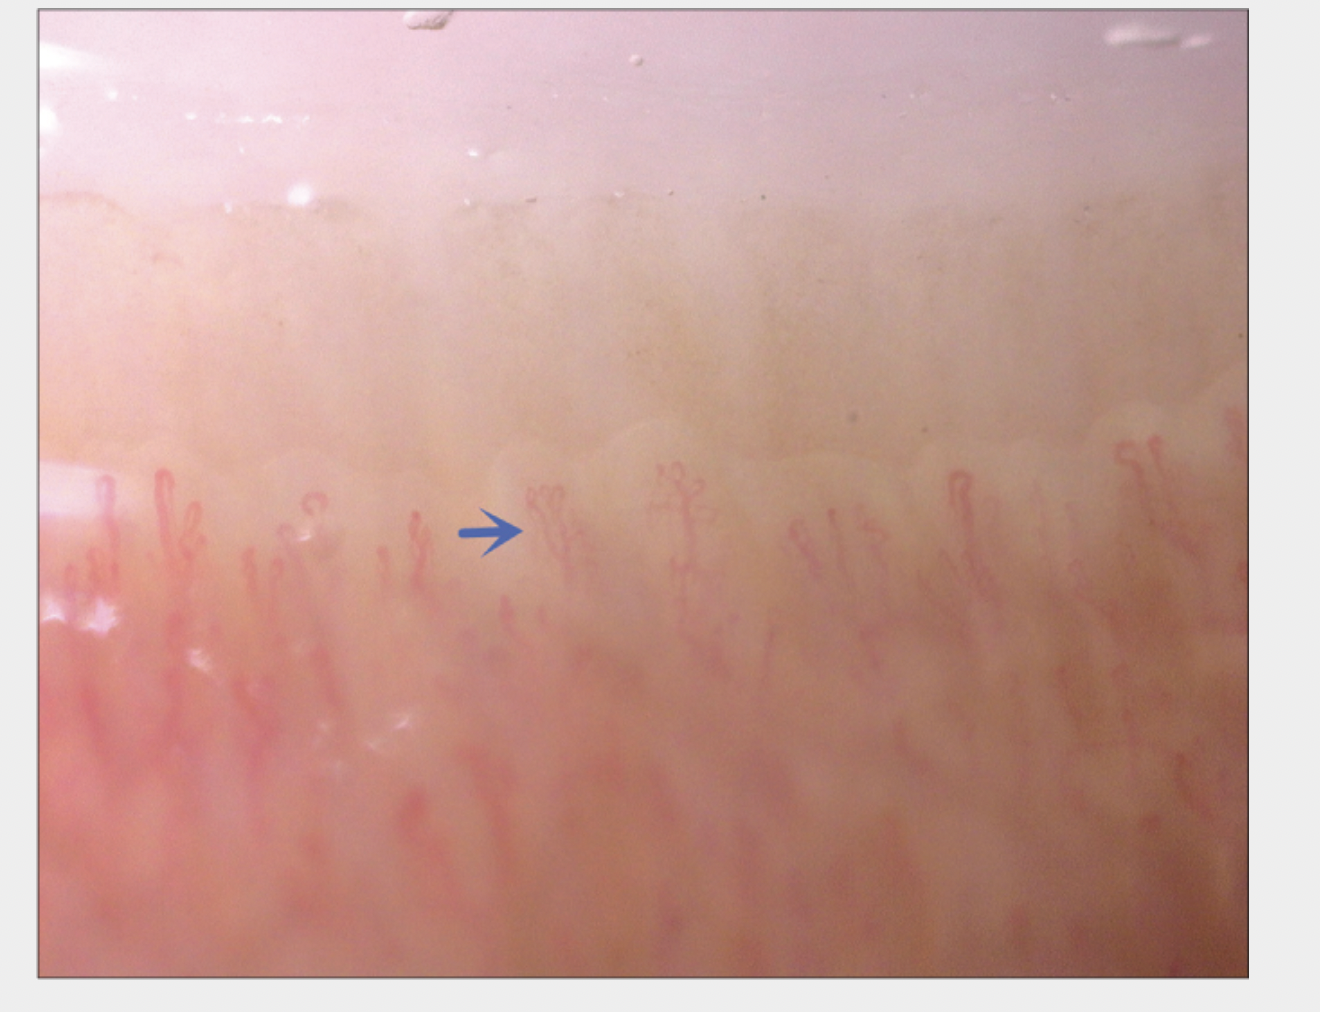

Examples of Capillaries Abnormalities More Commonly Seen In Androgenetic Alopecia

Normal capillaries. this image is a helpful reference. Source: Cao L et al. Nailfold capillaroscopy alterations in androgenetic alopecia: A cross-sectional study. Indian J Dermatol Venereol Leprol. 2022 Feb 28;1-7. Image shown with creative commons license.

BUSHY CAPILLARIES

Bushy capillaries are More Common in Nail Capillaries from Patients with Androgenetic Alopecia Compared to Controls. Source: Cao L et al. Nailfold capillaroscopy alterations in androgenetic alopecia: A cross-sectional study. Indian J Dermatol Venereol Leprol. 2022 Feb 28;1-7. Image shown with creative commons license.